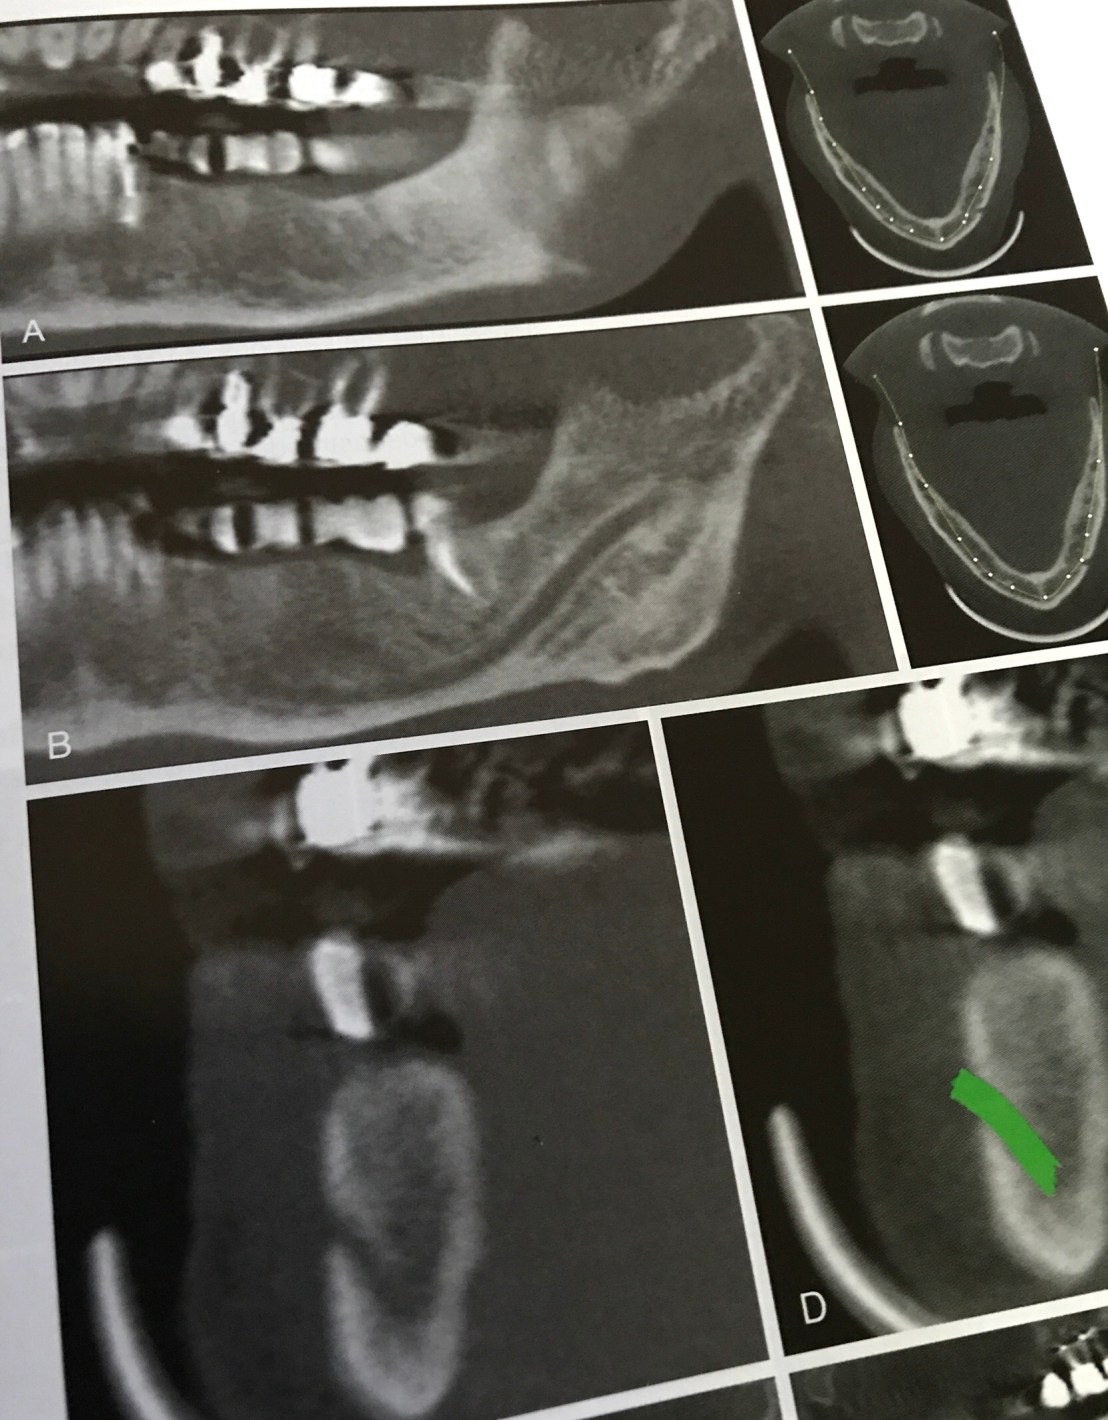

ตัวอย่างของการอ่านภาพ CBCT

รูป A และ B คือการใช้ Panoramic view หา Man. canal

รูป C และ D ใช้ Cross section view จนพบ Mental foramen ลูกศรเขียวคือ path ของ Mental nerve

รูป H คือ การวาด path ที่สมบูรณ์ของ Inf alv nerve, Mental foramen และ ตำแหน่งการวาง Prosthesis